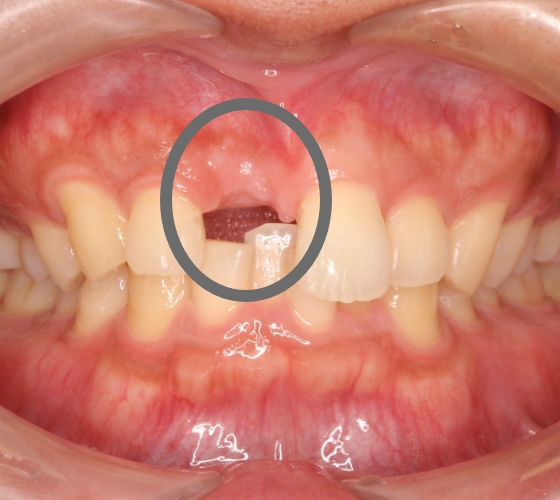

55歳男性 腫れて痛む

治療内容 以前他院で根管治療(根の治療)をした歯が、歯肉の腫れと排膿(膿が出る)や痛みが再発した症例です。

レントゲン写真で根尖部(根の先)に明らかな透過像(病変)を認めたため、再根管治療(根の治療)を行いました。

マイクロスコープ(顕微鏡)を用いて、ラバーダム防湿下で根管内を徹底洗浄・消毒後、根管を緊密に再封鎖しました。

治療後は腫れや痛みが速やかに消失し、レントゲン上でも根尖部(根の先)の透過像(病変)が著しく縮小したのを確認しました。

治療回数 2~5回

治療費用(総額)

保険治療でおおよそ2,000〜5,000